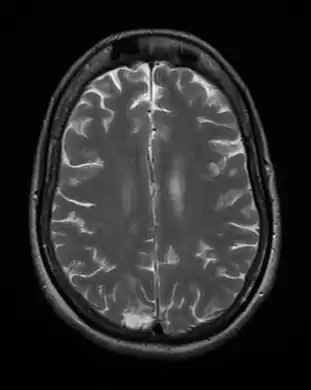

Acute

Acute toxoplasmosis is often asymptomatic in healthy adults.[13][14] However, symptoms may manifest and are often influenza-like: swollen lymph nodes, headaches, fever, and fatigue,[15] or muscle aches and pains that last for a month or more. It is rare for a human with a fully functioning immune system to develop severe symptoms following infection. People with weakened immune systems are likely to experience headache, confusion, poor coordination, seizures, lung problems that may resemble tuberculosis or Pneumocystis jiroveci pneumonia (a common opportunistic infection that occurs in people with AIDS), or blurred vision caused by severe inflammation of the retina (ocular toxoplasmosis).[15] Young children and immunocompromised people, such as those with HIV/AIDS, those taking certain types of chemotherapy, or those who have recently received an organ transplant, may develop severe toxoplasmosis. This can cause damage to the brain (encephalitis) or the eyes (necrotizing retinochoroiditis).[16] Infants infected via placental transmission may be born with either of these problems, or with nasal malformations, although these complications are rare in newborns. The toxoplasmic trophozoites causing acute toxoplasmosis are referred to as tachyzoites, and are typically found in bodily fluids.[17][18]

Due to the absence of obvious symptoms,[13][14] hosts easily become infected with T. gondii and develop toxoplasmosis without knowing it. Although mild, flu-like symptoms occasionally occur during the first few weeks following exposure, infection with T. gondii produces no readily observable symptoms in healthy human adults.[7][21] In most immunocompetent people, the infection enters a latent phase, during which only bradyzoites (in tissue cysts) are present;[22] these tissue cysts and even lesions can occur in the retinas, alveolar lining of the lungs (where an acute infection may mimic a Pneumocystis jirovecii infection), heart, skeletal muscle, and the central nervous system (CNS), including the brain.[23] Cysts form in the CNS (brain tissue) upon infection with T. gondii and persist for the lifetime of the host.[24] Most infants who are infected while in the womb have no symptoms at birth, but may develop symptoms later in life.[25]

The classic triad of congenital toxoplasmosis includes: chorioretinitis, hydrocephalus, and intracranial arteriosclerosis.[65] Other consequences include sensorineural deafness, seizures, and intellectual disability.[66]Congenital toxoplasmosis may also impact a child's hearing. Up to 30% of newborns have some degree of sensorineural hearing loss.[67] The child's communication skills may also be affected. A study published in 2010 looked at 106 patients, all of whom received toxoplasmosis treatment prior to 2.5 months. Of this group, 26.4% presented with language disorders.[68]